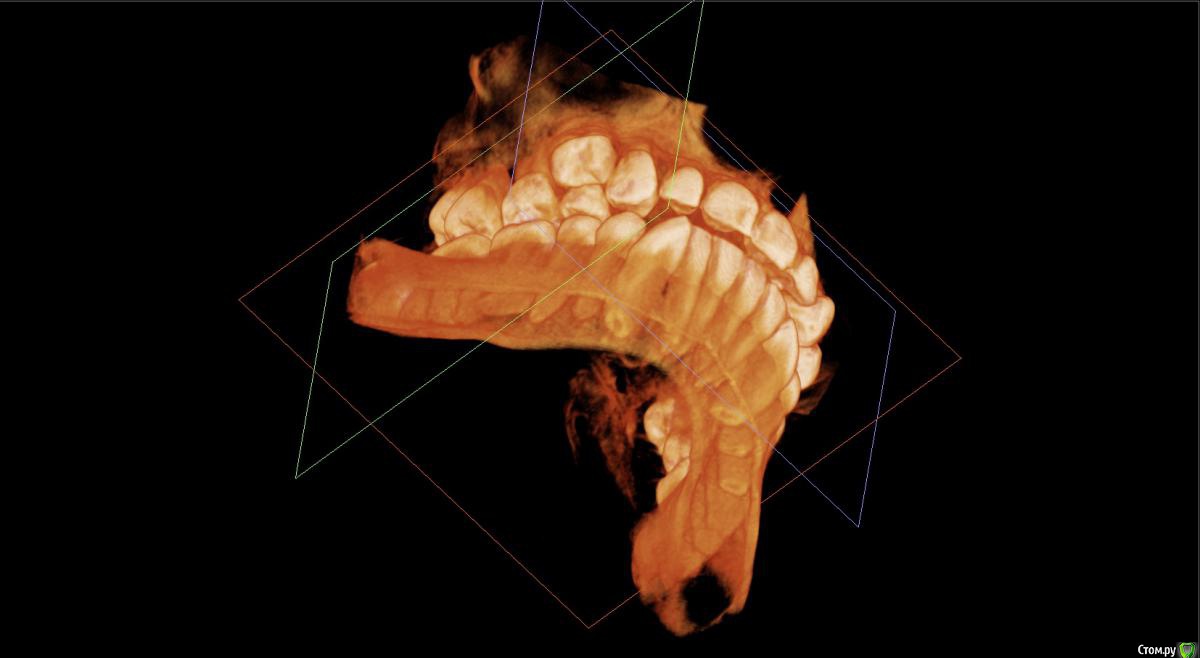

kamranchick Опубликовано 12 декабря, 2014 Поделиться Опубликовано 12 декабря, 2014 Добрый день девочки и мальчики Имеется следующая проблема.Пациент попросил удалить зуб 1.4(дистопированный) я удалил зуб, убрал вестибулярную стенку, а как восстановить десну, потому что очень большая "дырка" образовалась? я положил альвостаз жгутик и зашил вестибулярно Prolene 5/0.Вопрос. надо ли что то делать по косметики? либо так оставить, что "дырка" зарастет?! и стоило ли аументировать? он придет на снятие швов во вторник, какие дальнейшие действия мои должны быть.СпасибоПациент 14 лет, юноша. Ссылка на комментарий

Ayrat_zub Опубликовано 16 декабря, 2014 Поделиться Опубликовано 16 декабря, 2014 Хотелось бы услышать мнение представителя ортодонтов по поводу варианта с неудалением.вариант наиболее оптимальный был бы) и центральную линию нормализовать появилась бы возможность, и соответственно положение нч улучшить,судя по крайне ограниченным данным конечно) 4 Ссылка на комментарий